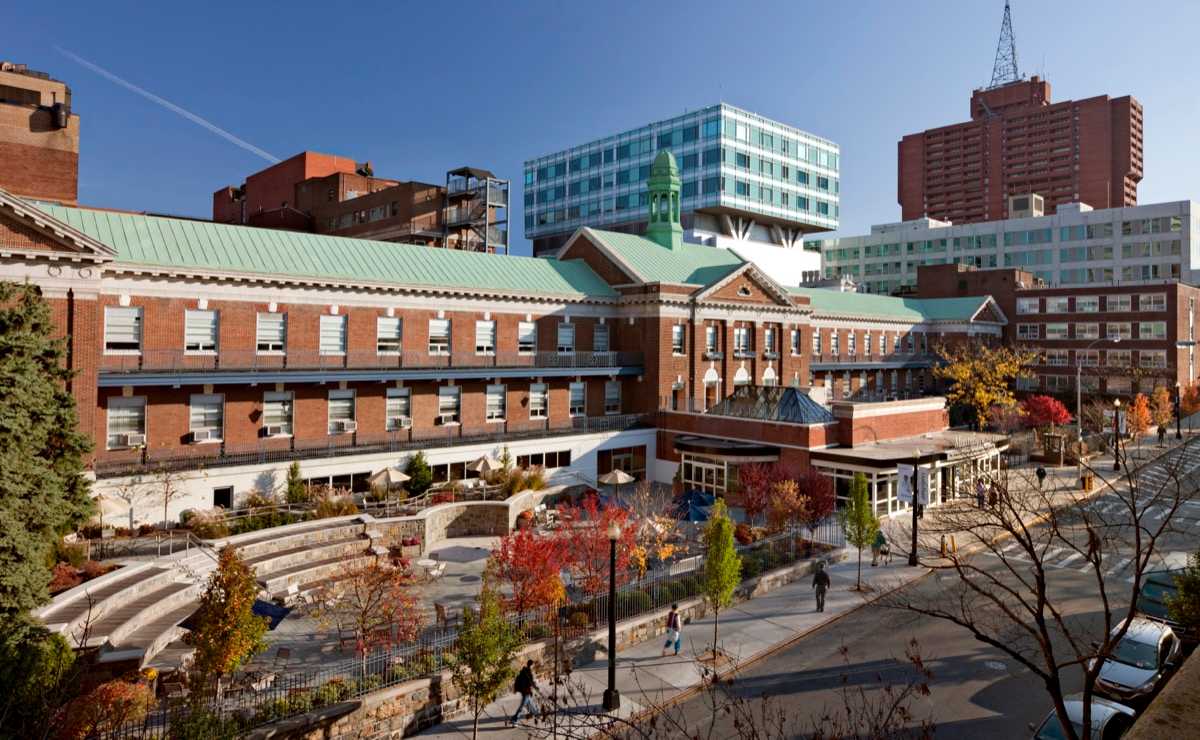

Our primary training home—home to notable programs and Montefiore Einstein’s Centers of Excellence

Moses Campus is the primary teaching site for our training programs. Our sub-specialty reading rooms serve as a hub for active clinical care and teaching, and support tertiary-level referral programs throughout the entire breadth of adult and pediatric medicine. In addition to specialized reading rooms, residents have full access to our resident library and a newly renovated resident lounge, and are invited to take advantage of our 3D imaging lab. Resident conferences are presented in-person from Binswanger Auditorium, although we electronically simulcast lectures and conferences from Moses to all our clinical sites. Resident learning is enhanced through participation in a range of interdisciplinary tumor boards and research programs.